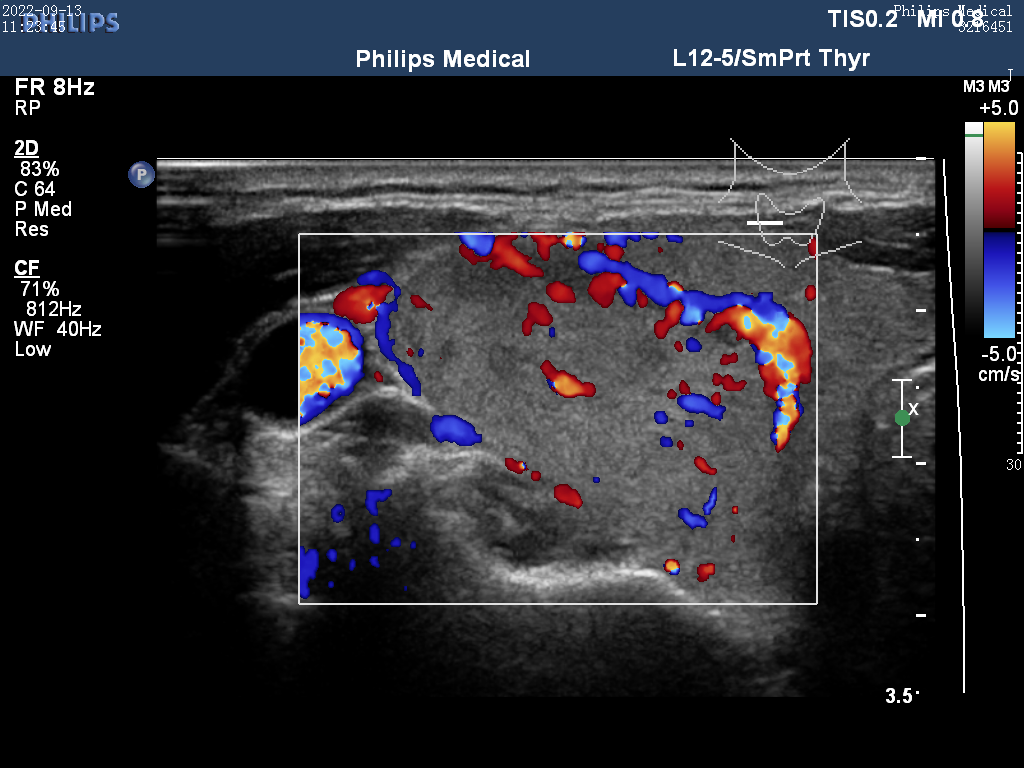

Ultrasound

ID: dc1776fa-ab41-4b71-a7e3-4ca9fa8f1cc3...dc1776fa-ab41-4b71-a7e3-4ca9fa8f1cc3

25 yoshli Erkak

30.11.2025 18:59

Yuqori

Tashxis

Malignant (Xavfli)

Saraton xavfi aniqlandi - Zudlik bilan onkolog va endokrinolog bilan bog'laning!

Ishonch

100,0%

TSH

2,5

Tugun

1,5 sm

Yuklab olingan (26x)

Ko'rish